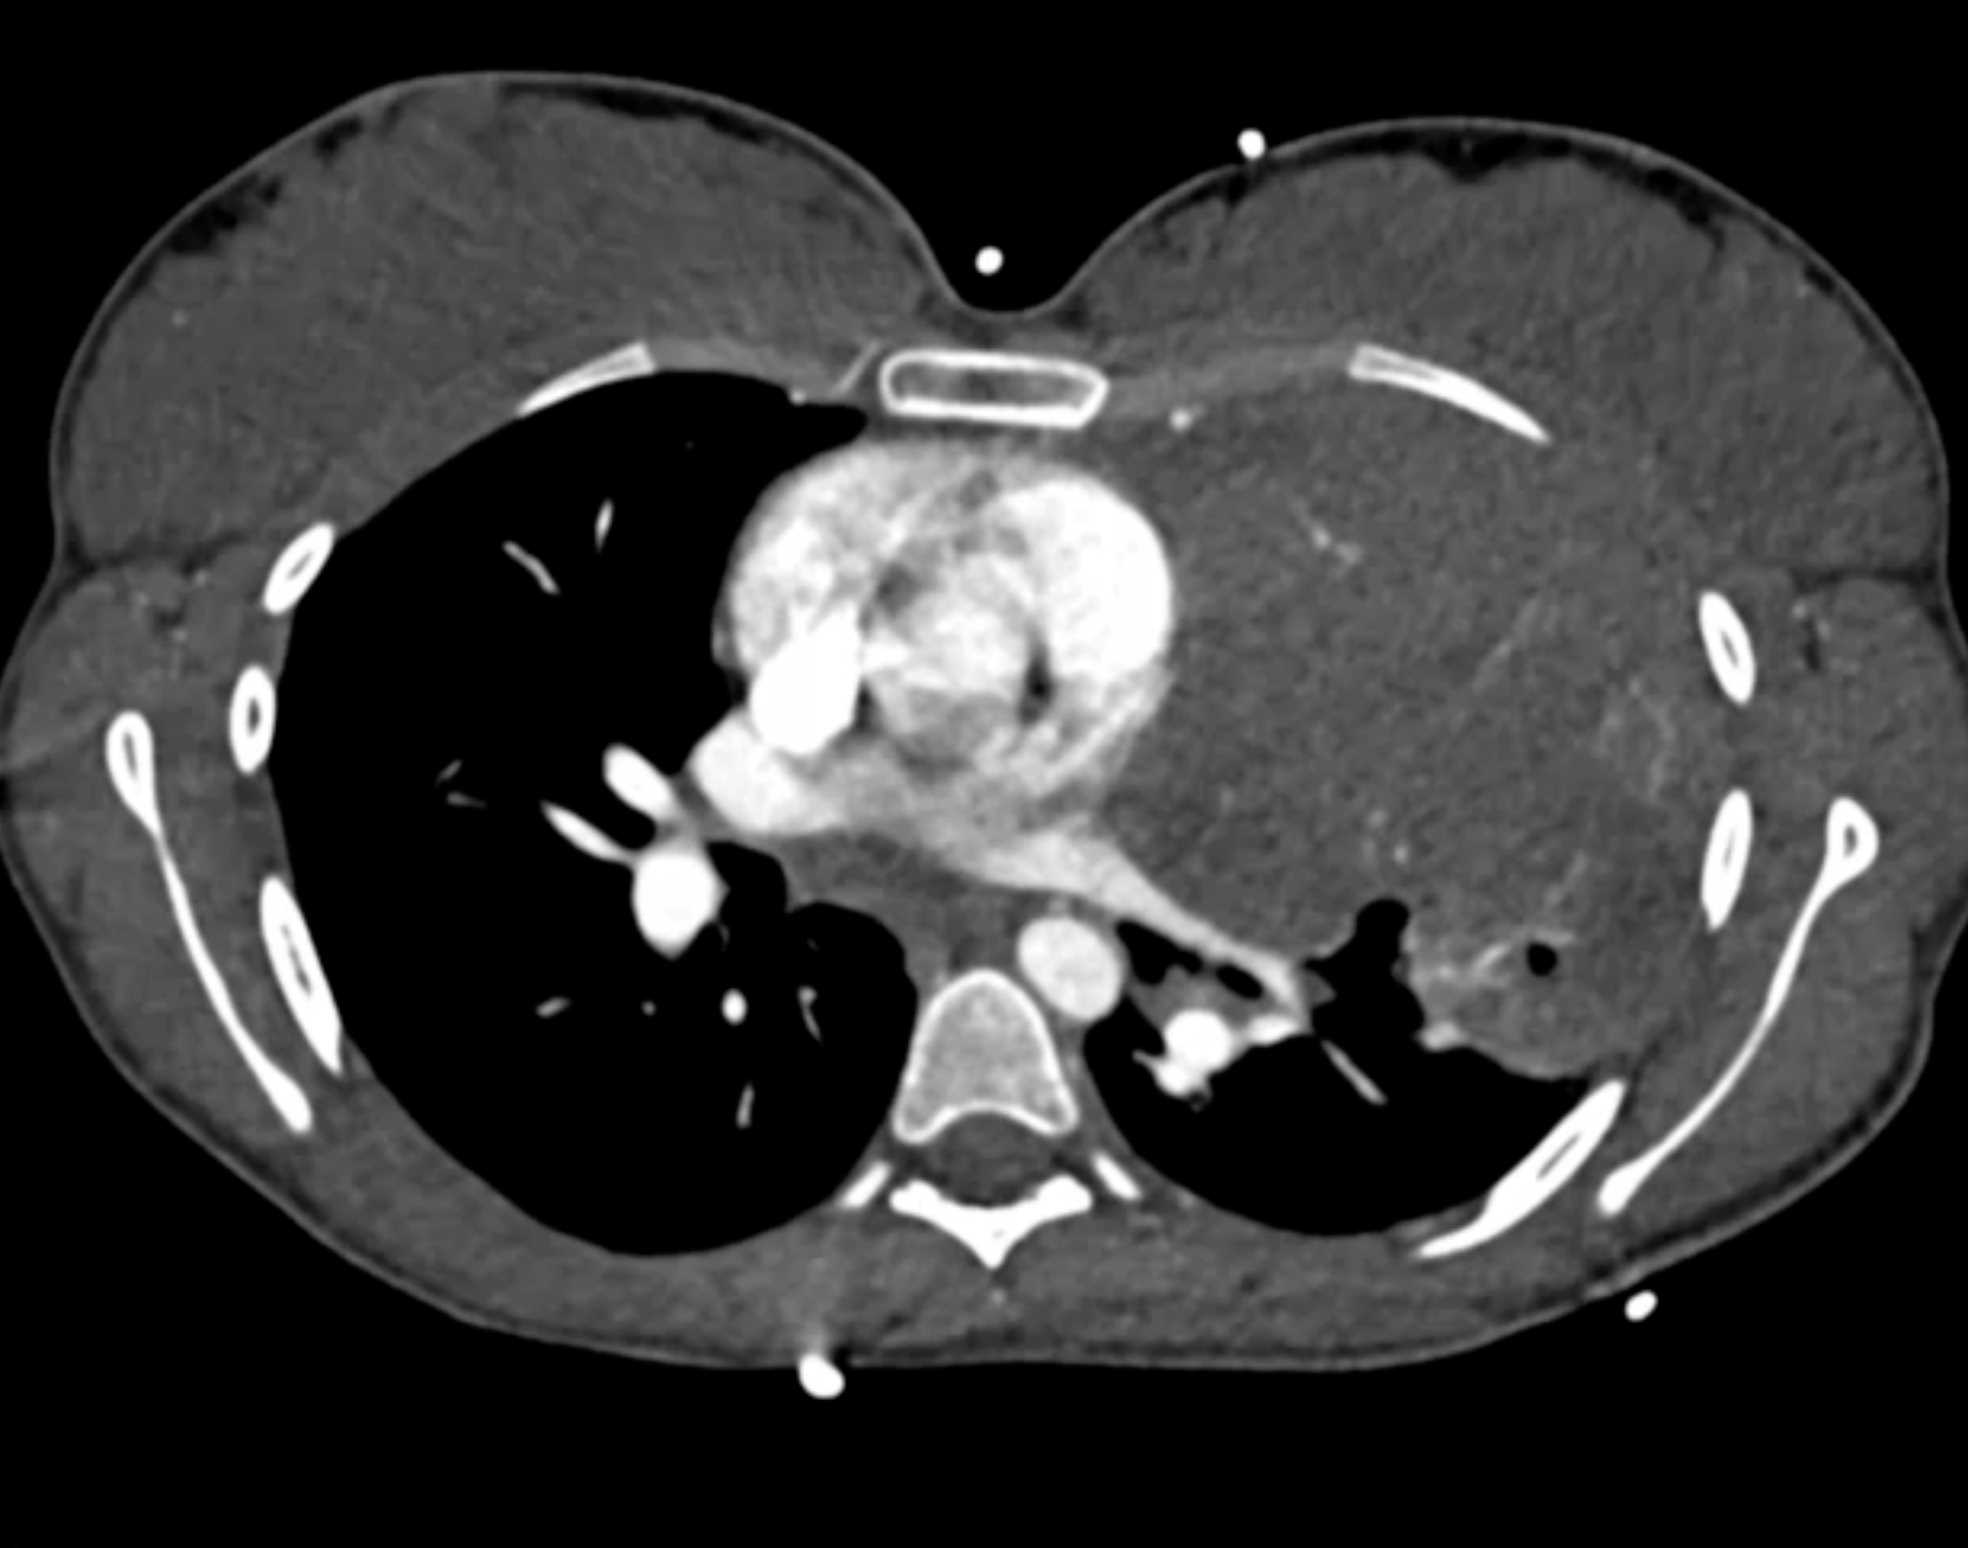

Subtle Adenocarcinoma Pancreas